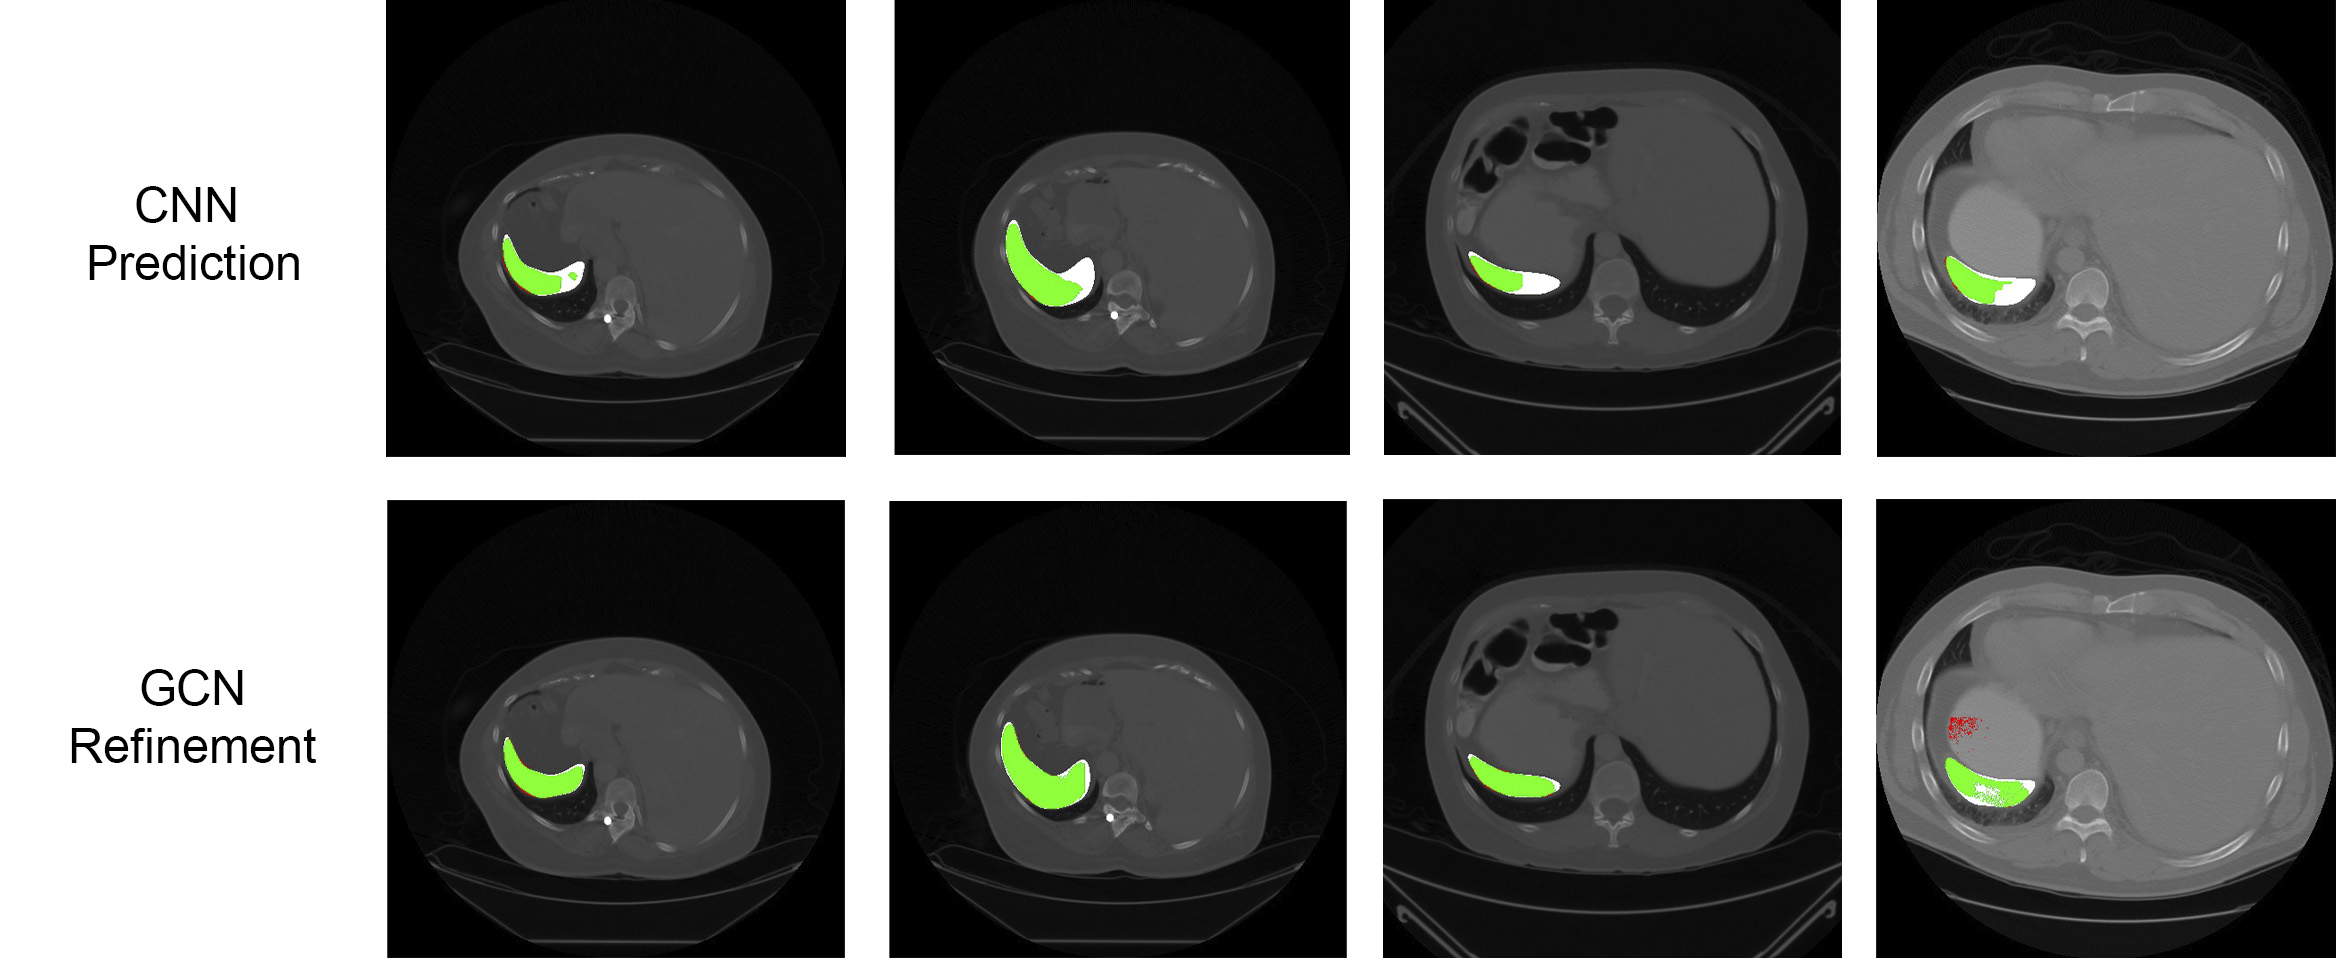

Refer to caption

Figure 4: Comparison of the CNN prediction and its corresponding GCN refinement for spleen segmentation. Green colors indicate true positives (TP), red indicates false positives (FP), and white false negative (FN) regions. From left to right: the first, second, and third columns show FN regions recovered. The fourth column shows an FN region recovered but also a new FP region generated.

Results are presented in Table 1. The GCN-based refinement outperforms the base CNN model and the CRF refinement by around 1% and 0.6% respectively in the pancreas segmentation task. For spleen segmentation, our GCN refinement presented an increase in the dice score of 2% with respect to the base CNN, and 1.7% with respect to the CRF refinement. Figs. 3 and 4 show visual examples of the GCN refinement compared with the base CNN prediction.